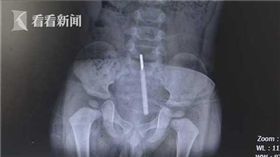

1歲半男童量肛溫 把溫度計坐入直腸

真的快嚇死!浙江溫州一名母親幫1歲半兒子量體溫,男童...

2018/06/06 19:32